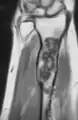

MRI showing enchondromas localized in the lower part of the radius of a 37-year-old patient affected with Ollier disease

MRI showing enchondromas localized in the lower part of the radius of a 37-year-old patient affected with Ollier disease.